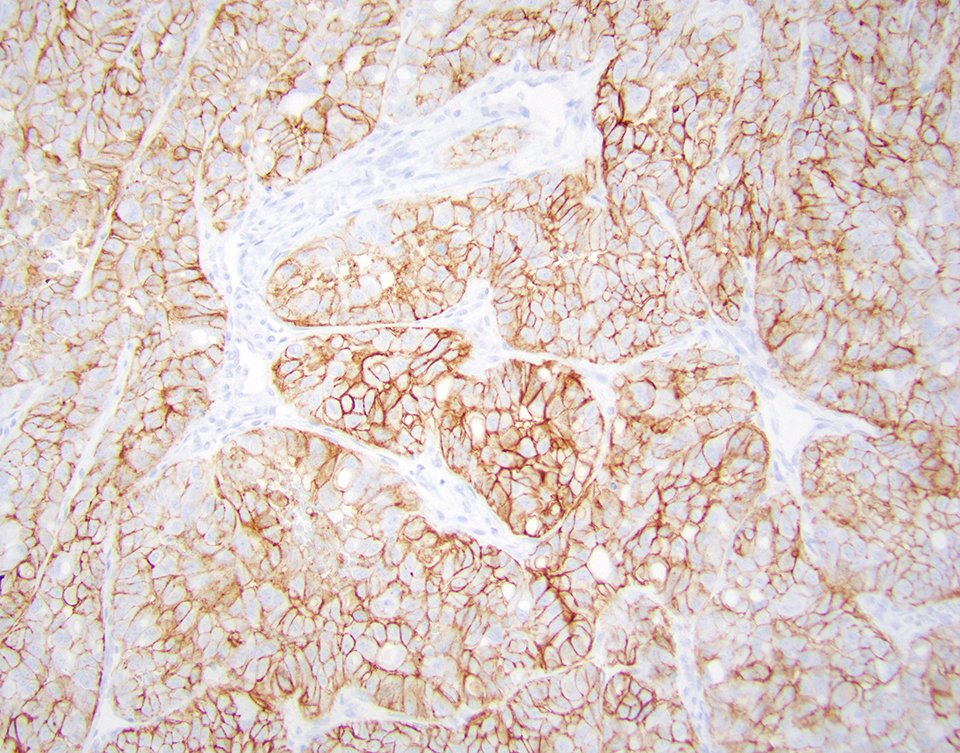

💥Diagnostic Pitfall Alert 💥 ➡️Diffuse CA9 expression in ~20% of FH-deficient RCCs ➡️Pitfall likely greater in metastatic lesions vs primary renal tumor #gupath #GUpathrocks 🔬 Baniak N et al, Histopathol 2020 - PMID: 32639054 Pacheo RR et al, IJSP 2024 - PMID: 37050851